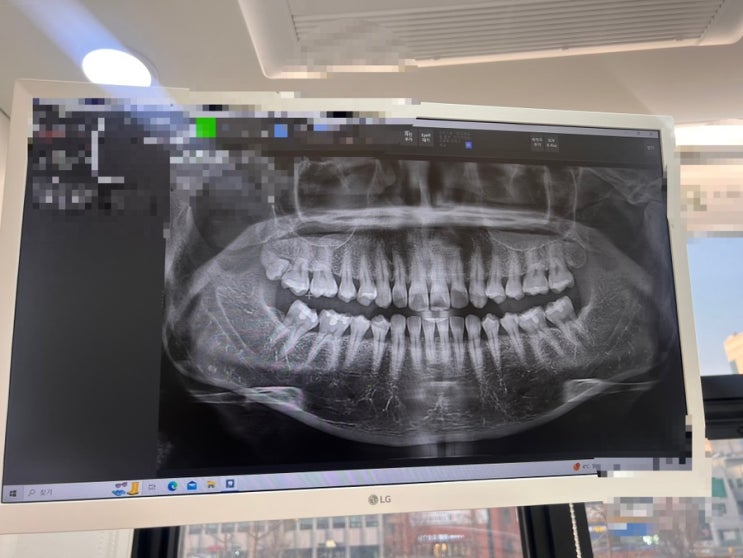

무서운 사랑니 발치

마취하고 대기 중 생전 처음 빼보는 사랑니 왜케 늦게 난거냐 나는 ㅋㅋㅋ